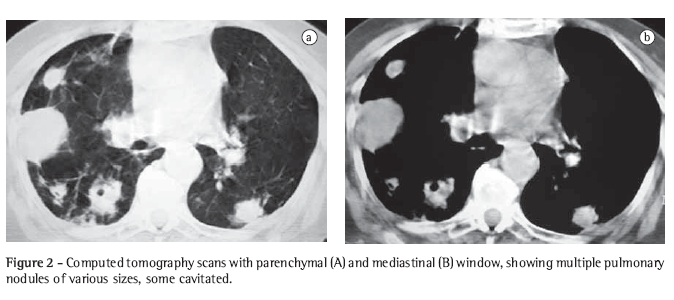

A computed tomography (CT) scan of the chest revealed nodules, some cavitated, of various sizes (Figure 2). Three sequential sputum samples were tested for acid-fast bacilli and fungi (silver staining), and the results were negative. In the three sputum samples collected, smear microscopy (Gram staining) revealed filamentous bacteria, strongly suggestive of Nocardia spp., which was confirmed by Ziehl‑Neelsen staining, showing the characteristic partial acid-fastness (Figure 3).

The chest X-ray presentation of pulmonary nocardiosis is nonspecific. The most common radiological findings are consolidations and large irregular nodules. Nodules, cavitated masses, pleural effusion, pneumothorax, ground-glass opacities and interstitial patterns can occur as well.(1,4,5,11) Some studies show that, in HIV-infected patients, there is a higher percentage of cavitated lesions.(8) Alveolar consolidation in the upper lobes is often confused with pulmonary tuberculosis.(6) Although the alterations observed on CT scans are similar to those of the conventional X-rays, CT is superior in demonstrating the exact location and extent of the lesions, as well as in the differentiation between pulmonary and pleural lesions.(5) In the case reported, the patient presented nodules of various sizes, disseminated throughout both lungs, and some of those nodules were cavitated.